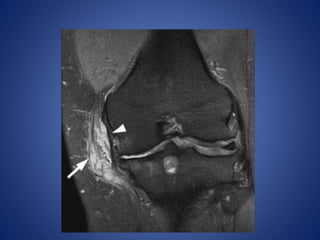

• #24 PCL ganglion. A 28-year-old male with persistent pain after injury. Sagittal T2W fat-saturated image demonstrates multilobulated cystic lesion (arrow) involving distal posterior cruciate ligament